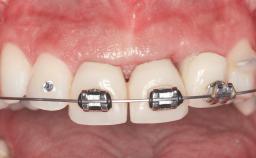

A 30-year-old woman was referred by her general dentist for evaluation of an esthetic complication related to previous implant treatment for congenitally missing maxillary lateral incisors. The patient’s chief complaint was the inadequate esthetic appearance of her smile. The case demonstrates the use of a combined approach to achieve optimal results. Two different flap designs - a tunnel technique and a coronally advanced flap - are employed based on the surgical objectives for the affected site.